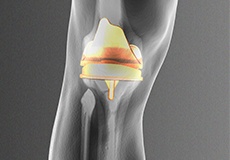

Total Knee Replacement

Total knee replacement, also called total knee arthroplasty, is a surgical procedure in which the worn out or damaged surfaces of the knee joint are removed and replaced with an artificial prosthesis.

Knee Implants

Knee implants are artificial devices that form the essential parts of the knee during a knee replacement surgery. The knee implants vary by size, shape, and material. Implants are made of biocompatible materials that are accepted by the body without producing any rejection response.